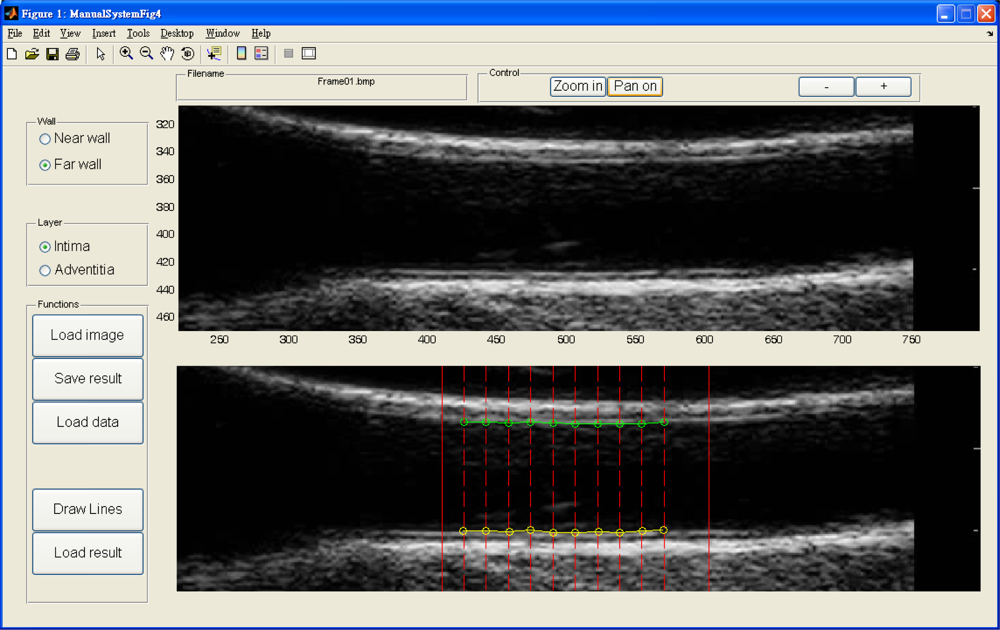

Figure 14 depicts our manual drawing GUI. The solid lines denote the boundary of the automated analysis. The dashed lines denote where the expert should give their judgment on the lumen-intima interface. Manual drawing involves a tremendous amount of human work. Although we are not able to provide many manual drawings for comparison, however, the automated results were controlled visually by experts and all results are similar to those shown in Tables 1 and 2. The system is built on the Matlab platform. Some kernel functions are written in C language in order to reduce the computation time.